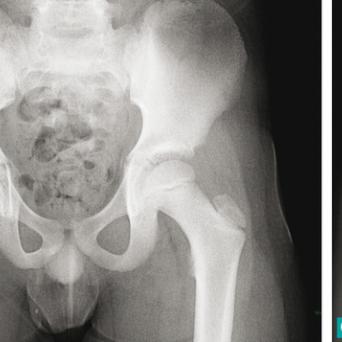

Lacertus fibrosus : à ne pas confondre avec le canal carpien !🎬

Le syndrome du lacertus fibrosus est une affection courante, mais encore largement méconnue. Souvent confondu avec le syndrome du canal carpien, son diagnostic est négligé ou posé tardivement, parfois après échec d’une chirurgie pour syndrome du canal carpien. Pourtant, certains signes sont caractéristiques et l’examen clinique permet de distinguer ces deux pathologies et d’orienter rapidement les patients. Flash interview du Dr Marc-Olivier Falcone, chirurgien orthopédiste et traumatologue, Paris.